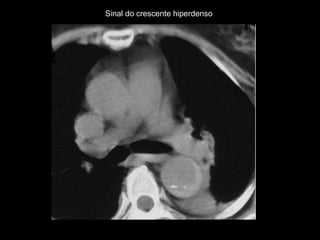

O sinal do crescente hiperdenso na parede da aorta

representa hematoma agudo com sangue contido

no interior do trombo do aneurisma;

Diagnosticado melhor na fase sem contraste;

Sinal do crescente hiperdenso